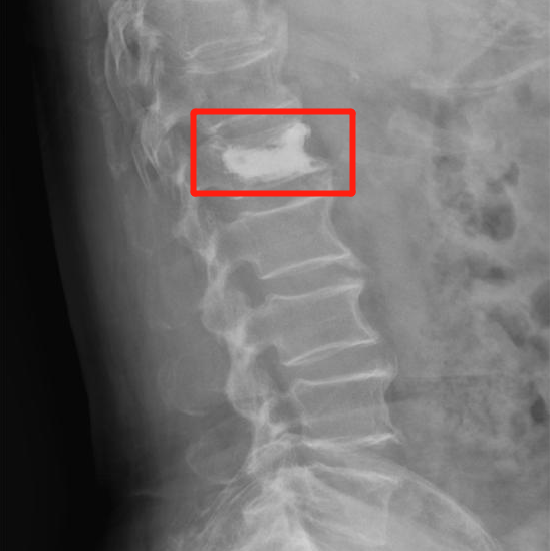

王阿姨入院后,谢主任为王阿姨进行了微创手术---腰椎椎体成形术。术后当天,王阿姨的腰痛就明显缓解,第二天就能下床正常活动了。

王阿姨术后X线图像